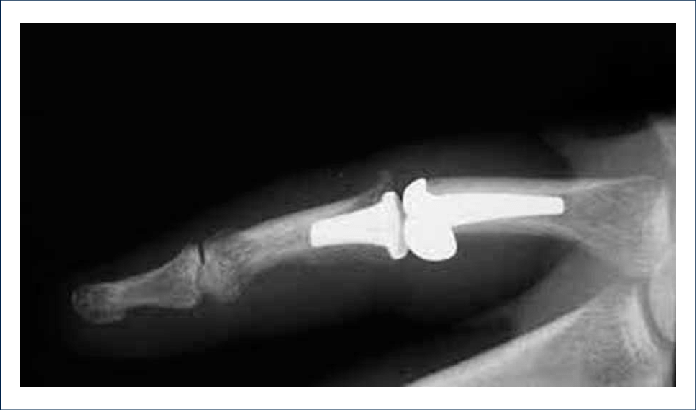

Se puede solicitar una Rx, donde se puede evidenciar daño de la articulación, formación de osteofitos, disminución del espacio articular o luxaxión de las falanges. Estos cambios se conocen como artropatía y ayudan a identificar que tan avanzado está el problema y saber el tratamiento apropiado.